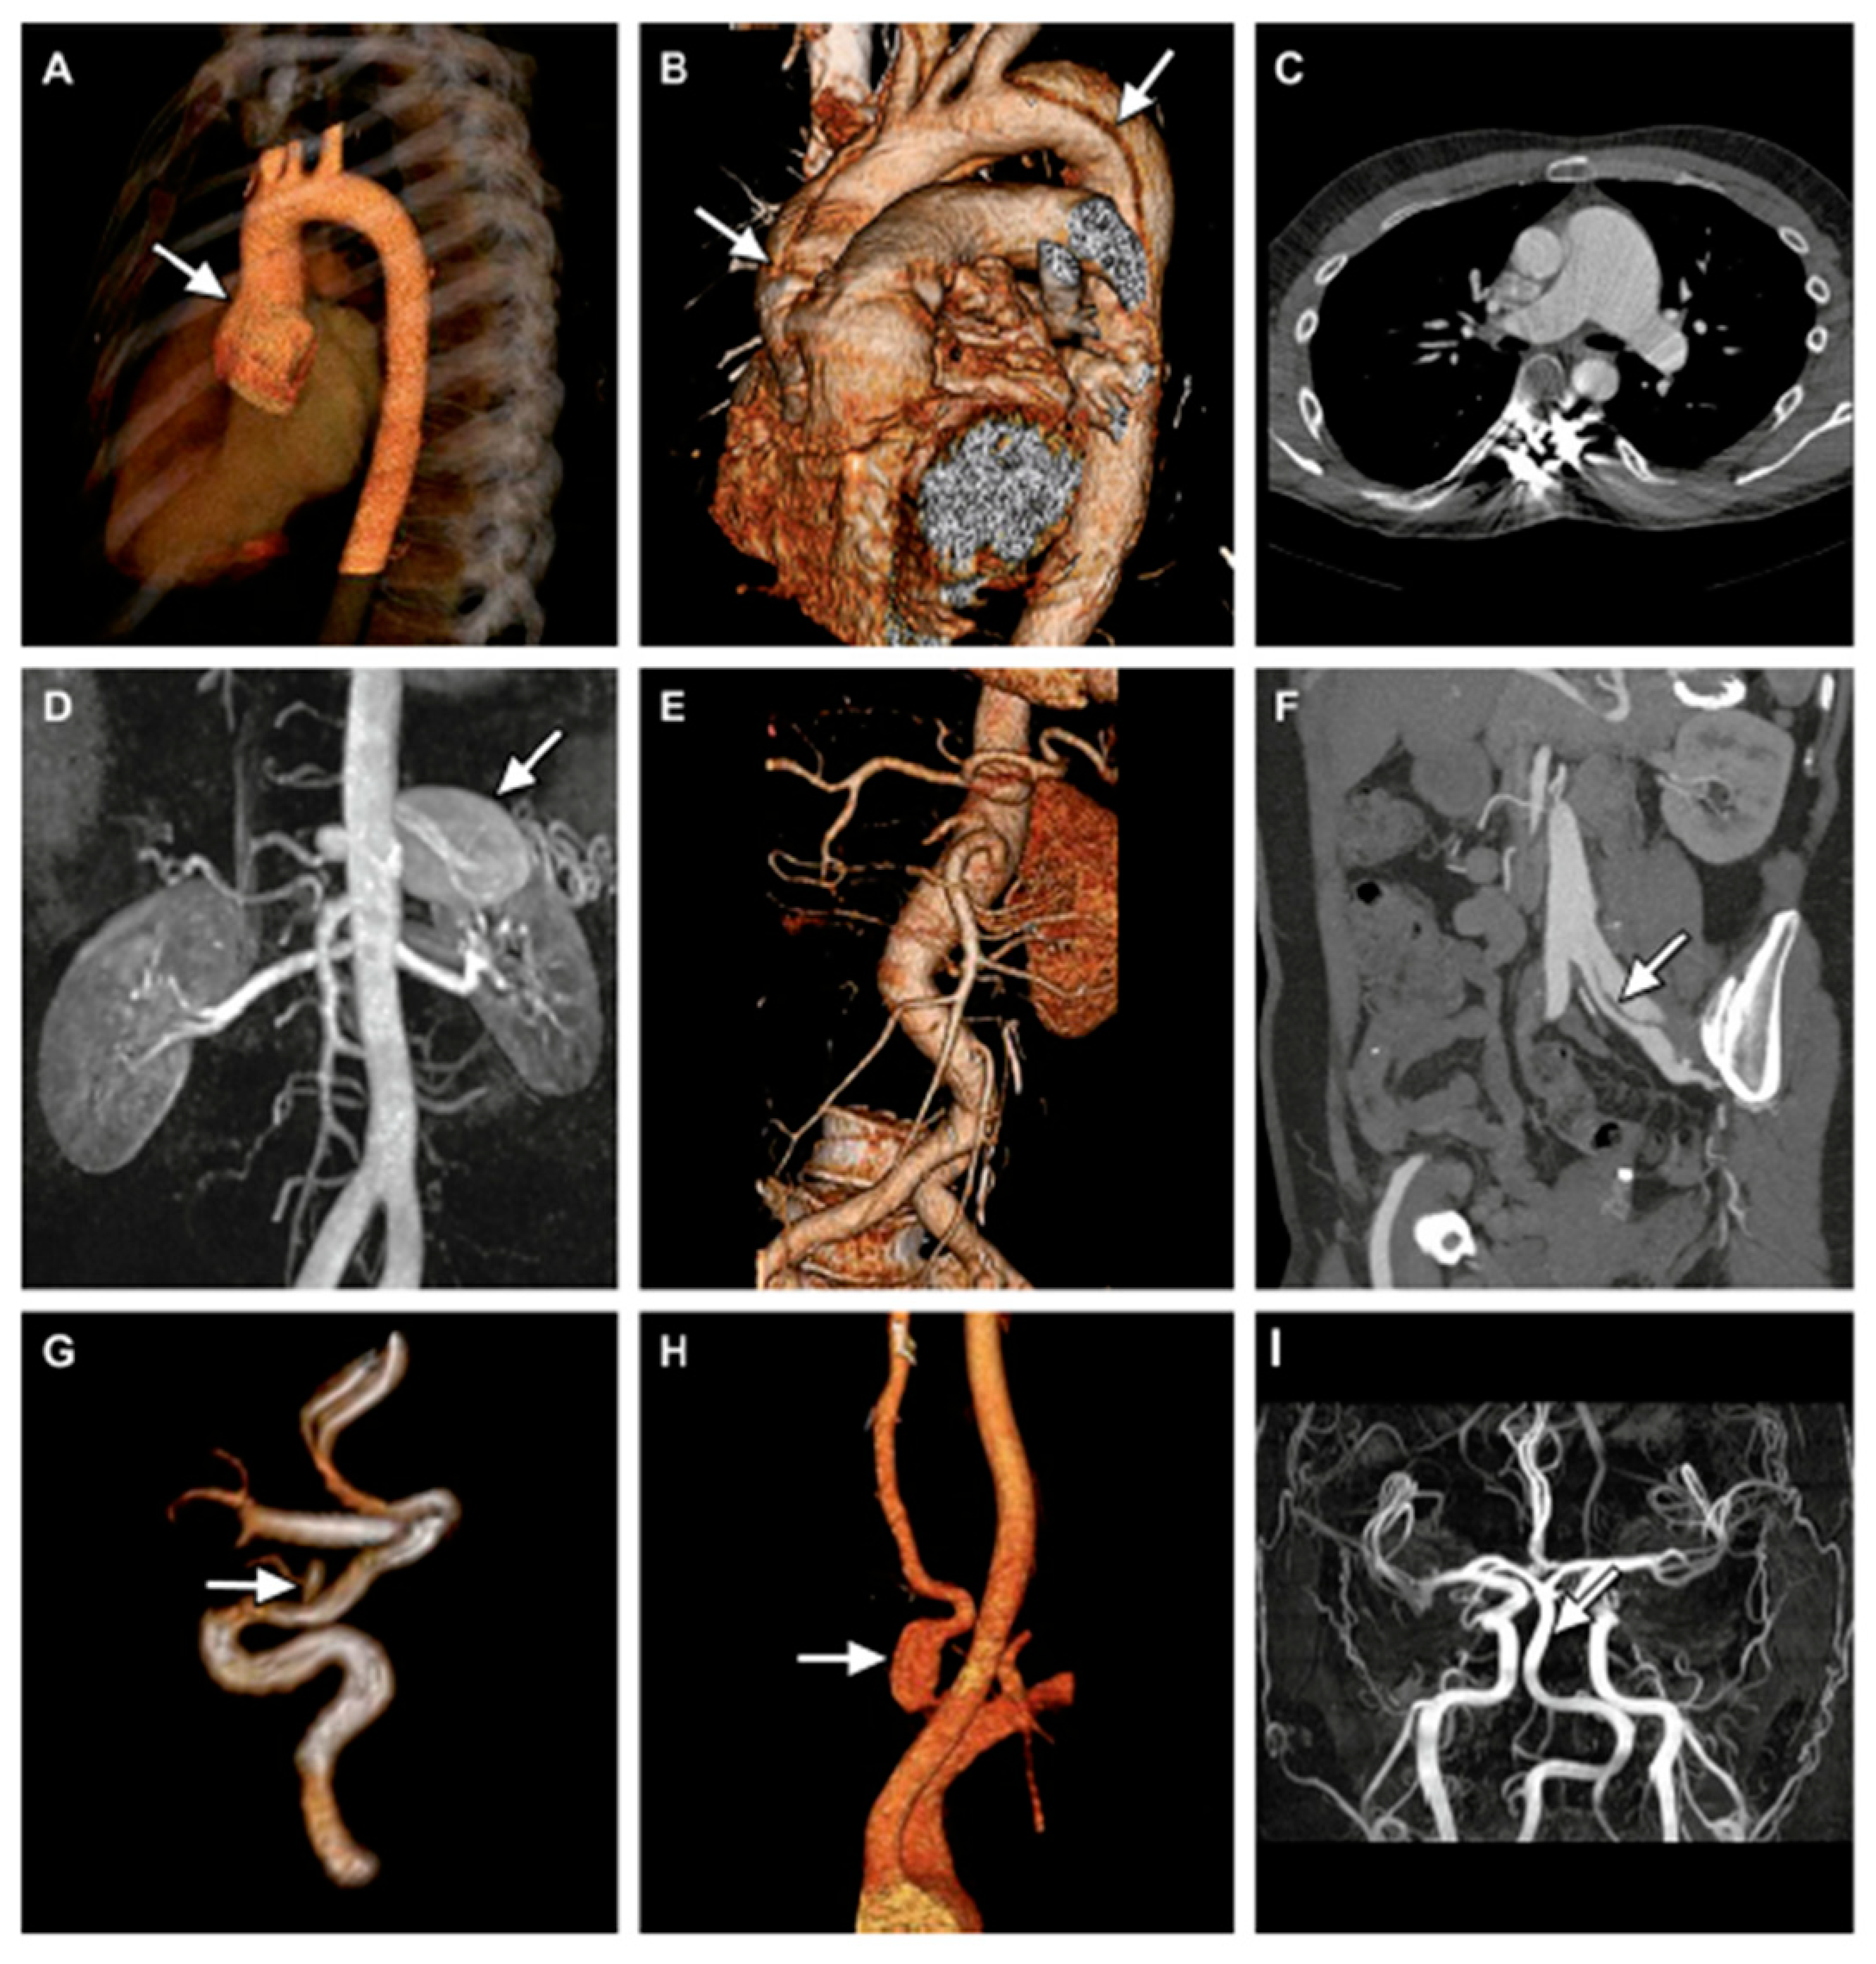

Whereas in MFS, aortic involvement mainly affects the aortic root and ascending aorta, in LDS there is more involvement of the epiaortic and cerebral vessels and mesenteric arteries (Figure 9) [42].

Figure 9.

Arterial anomalies in LDS. (A): Aortic root aneurysm by 3D CT angiography (CTA); (B) Stanford type A aortic dissection extending into the brachiocephalic trunk; (C) aneurysm of the truncus pulmonalis by CT; (D) aneurysm of the splenic artery by RMI; (E) tortuosity of the abdominal aorta, suprarenal aneurysm of the abdominal aorta and aneurysms of the coeliac trunk, and left common iliac artery by 3D CTA; (F) Stanford type B aortic dissection of abdominal aortic with dissection flap extending into the left common iliac artery; (G) saccular aneurysm of the right ophthalmic artery by RMI; (H) fusiform aneurysm of the left vertebral artery by 3D CTA; (I) fusiform dilatation of basilar artery by RMI. Adapted with permission from [42].

Furthermore, aneurysmal pathology in LDS is characterized by greater tortuosity of the vessels and higher fragility of the walls.